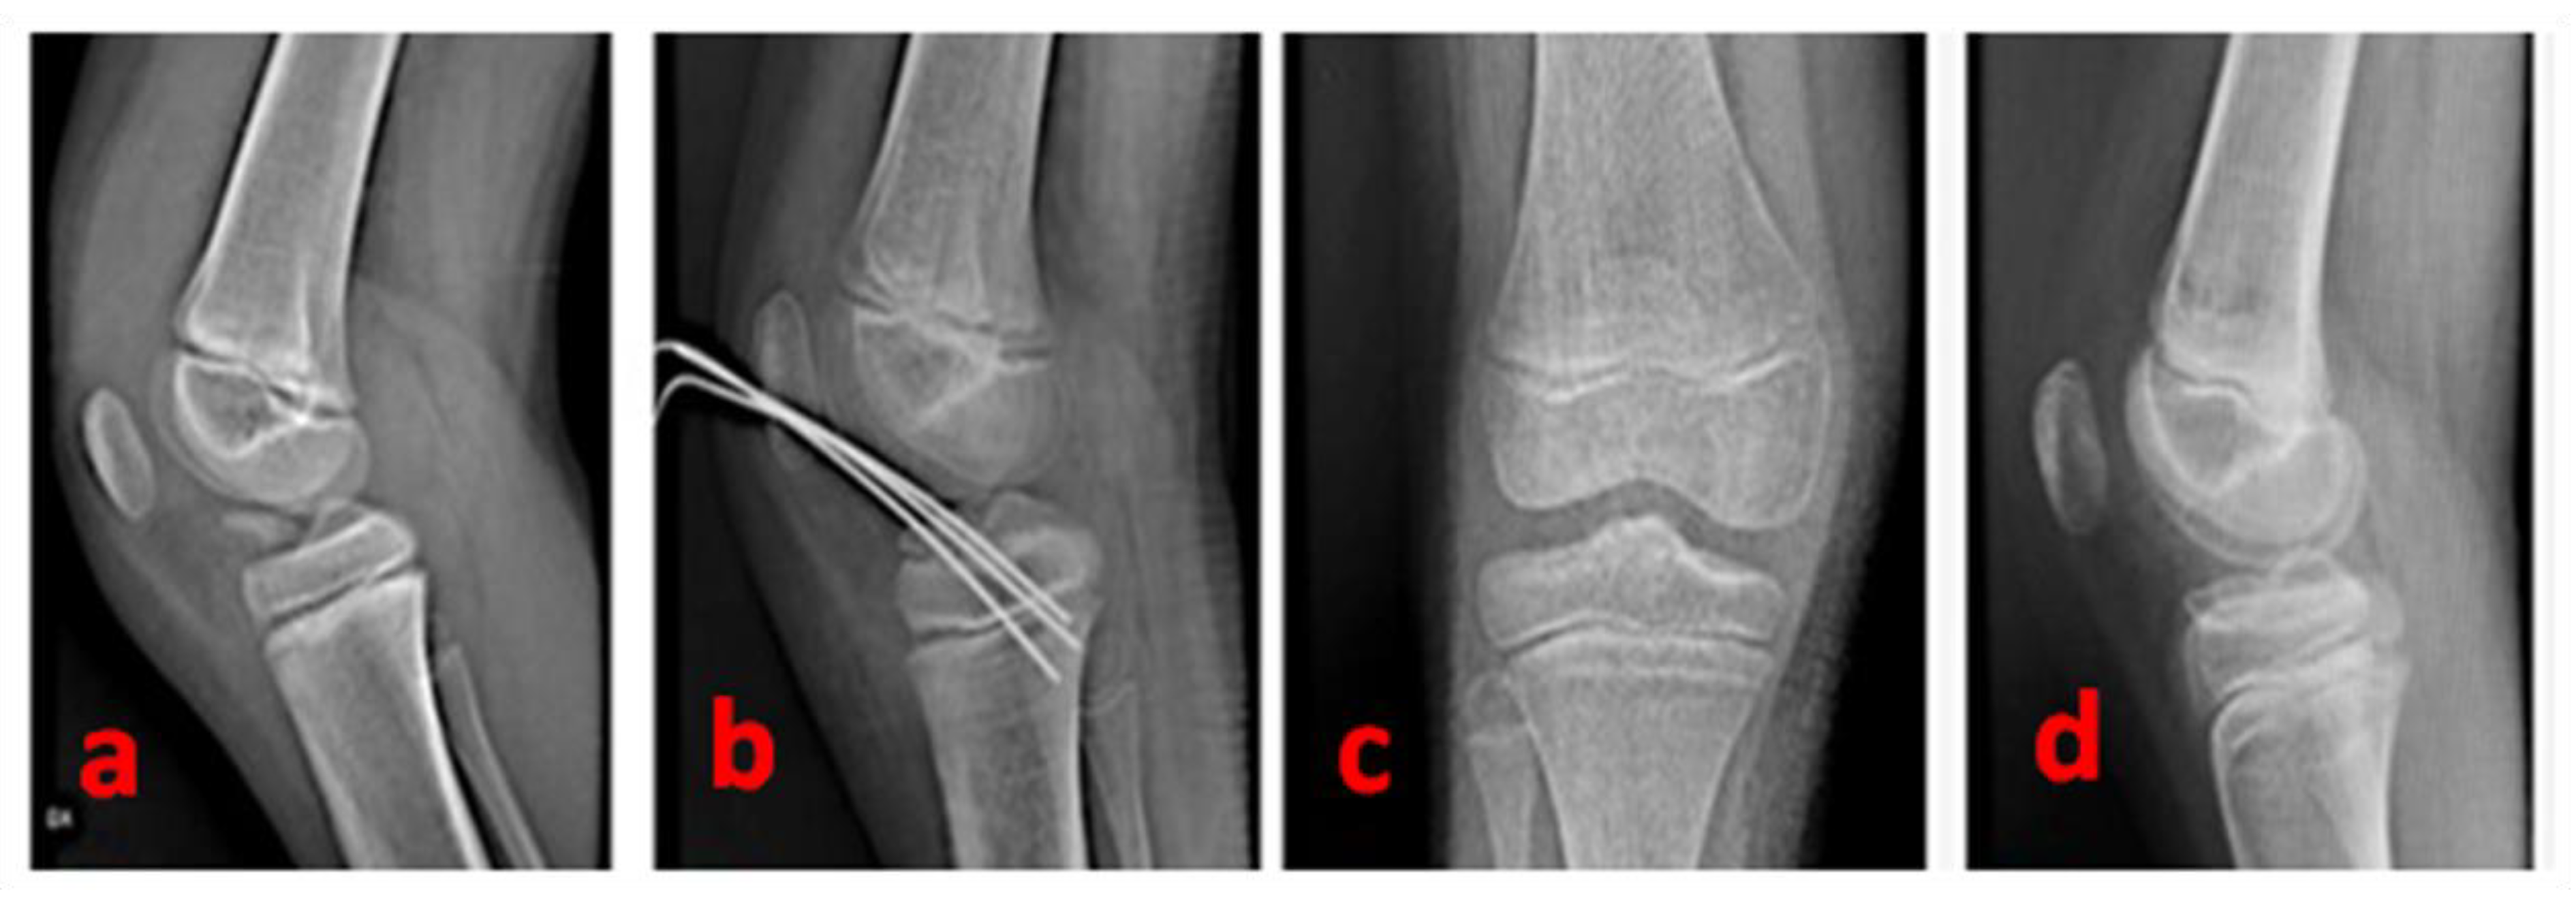

2.3. Approach and Fracture Fixation

3. Results